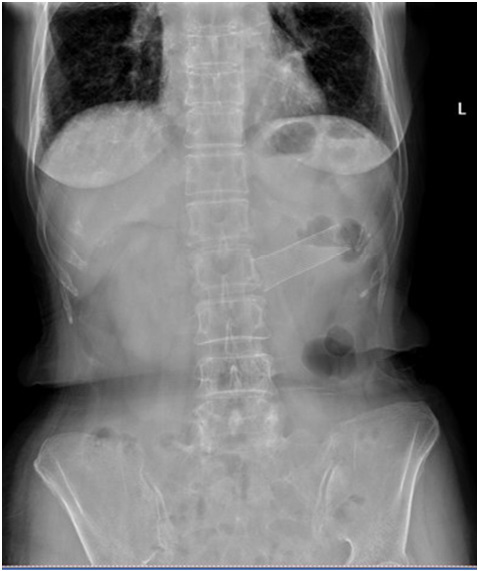

Figure 3: Re-examination of abdomen x-ray after self-expanding metal stent placement.

figure 3